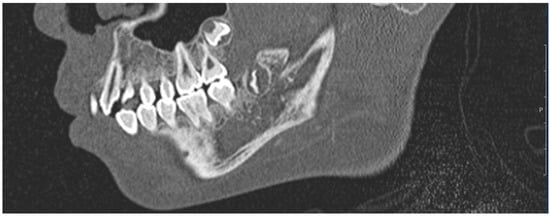

2. Materials and Methods

2.4. Design